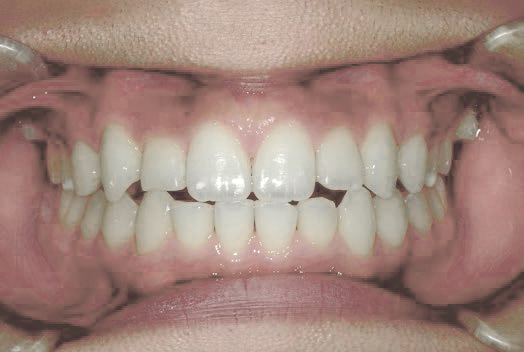

Before

After

上あごの成長が少なく、特に前歯のガタガタが目立っていました。口呼吸のクセや飲み込み方に良くないクセが確認されました。

治療を終えて

マイオブレイスとBB1装置で上あごの成長を助け、鼻呼吸や正しい飲み込み方を身につけることで、きれいな歯並びとしっかり噛めるお口に変わっていきました。

姿勢やお口の機能を正しく整えたので、後戻りしない綺麗な歯並びを維持できています。もちろん非抜歯です。

主訴・治療内容 当院と交流のある歯科医師の先生が、ご自身のお子さまの治療を任せてくださいました。

「難しい歯並びでも永久歯を抜かず、全身の健康と顔立ちも考えて治療してくれる」と信頼していただいて治療開始。

治療期間 3年

費用 462,000円(税込)

リスク・副作用

• 治療の初期段階では、痛みや不快感が生じやすくなりますが、一週間前後で慣れます。

• 歯の動き方には個人差があるため、予想された治療期間より延長する場合があります。